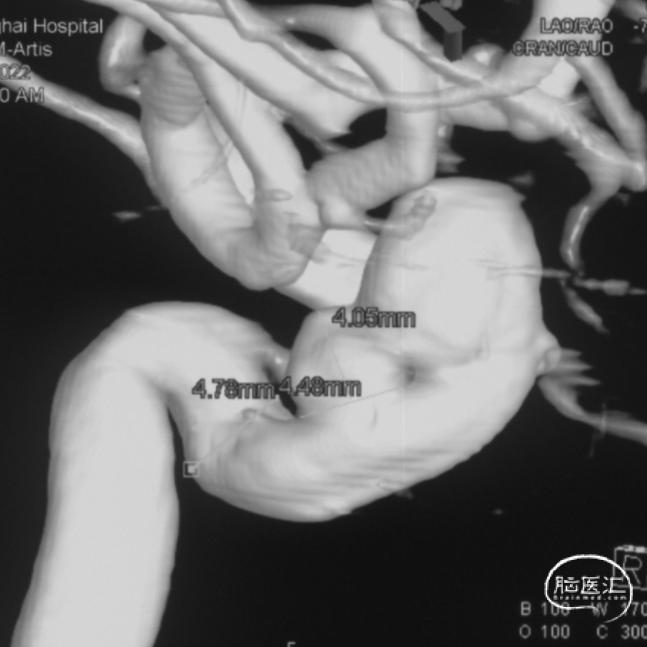

术前影像学资料

外院DSA

右侧颈内动脉眼动脉段-海绵窦段串联两枚动脉瘤,分别大小约:

① 8.8mm*5.9mm*5.2mm,瘤颈宽7.0mm;

② 6.8mm*4.3mm*3.6mm,瘤颈宽3.3mm。